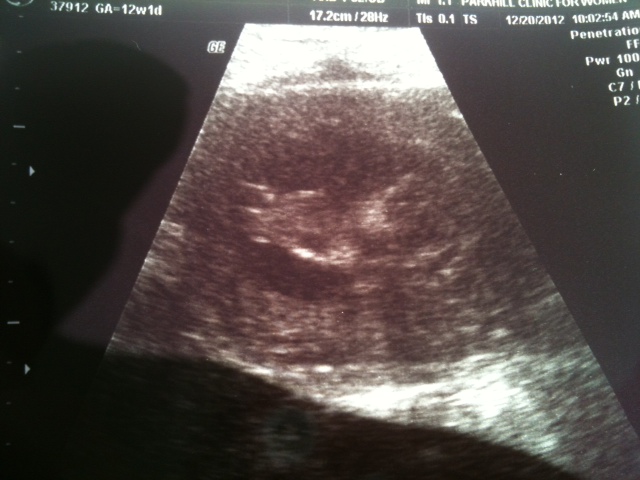

This is the best picture I got, I'm thinking I might be seeing a nub under the leg. Unless thats the other leg. I'm new to all this. What do you guys think?

I was 12w1d and the baby actually measured 12w5d :think:

Hard to tell in the first. I've seen a lot of US's, but this gestation is REALLY hard to tell. The head is on the right and legs on the left, but what's in between legs is too hard to tell-the angle is near impossible to tell gender ;) The second one it looks like the knees are up so you wouldn't be able to tell either way in that one either :) But, I am no expert. Were they able to tell you!? Fun looking and wondering - thanks! :)

Slight boy lean but I'm not positive that's a nub I'm seeing.